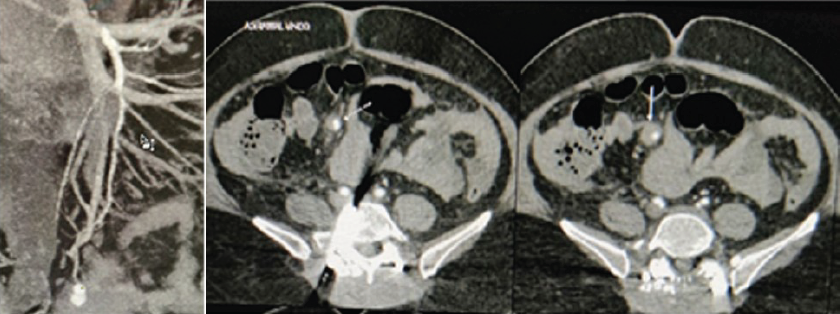

The procedure was successful, and the patient was monitored postoperatively. Two days after surgery, the patient developed acute pancreatitis, presenting with abdominal pain, vomiting, and elevated serum lipase levels (743 U/L, rising to 6231 U/L). Although the pancreas was obscured on ultrasound due to excessive bowel gas, the condition was managed conservatively, and the pancreatitis subsided within 6 days. Serial laboratory monitoring showed a rise in serum lipase from 743 U/L to 6231 U/L, followed by a gradual decline over the next week. Leukocytosis and inflammatory markers such as C-reactive protein were tracked and correlated with clinical recovery. The limited resolution of ultrasound due to bowel gas delayed clear visualization of the pancreas, and high-resolution imaging (such as early computed tomography [CT]) was not performed initially, which may have contributed to the diagnostic delay. On postoperative day 9, the patient experienced fever, tachycardia, and leukocytosis. Suspected causes included central venous catheter-related sepsis or a surgical site infection, though wound examination and blood cultures showed no signs of infection. Chest imaging revealed a right-sided pleural effusion, for which pleural tapping was performed, providing temporary relief. However, the patient’s condition worsened on postoperative day 12, with hypotension, breathlessness, and desaturation. Following a cardiology evaluation and a CT angiography, a vaso-vagal event was suspected. A gastroenterological review was initiated after the patient developed severe abdominal distension, vomiting, and a significant drop in hemoglobin levels. CT angiography of the abdomen revealed hemoperitoneum and evidence of active bleeding, with contrast extravasation suggesting a pseudoaneurysm of the SMA (Fig. 3).

Figure 3: Contrast-enhanced CT scan shows the pseudoaneurysm (white arrow) in one of the distal branch of the superior mesenteric artery

An urgent digital subtraction angiography confirmed the pseudoaneurysm, and selective catheterization of the affected artery was performed, followed by embolization using micro-coils. Post-procedure, the patient showed marked improvement, and hemoglobin levels were restored through multiple transfusions (Fig. 4).

Figure 4: Exclusion of the pseudoaneurysm is confirmed by selective SMA injection after coil deployment.